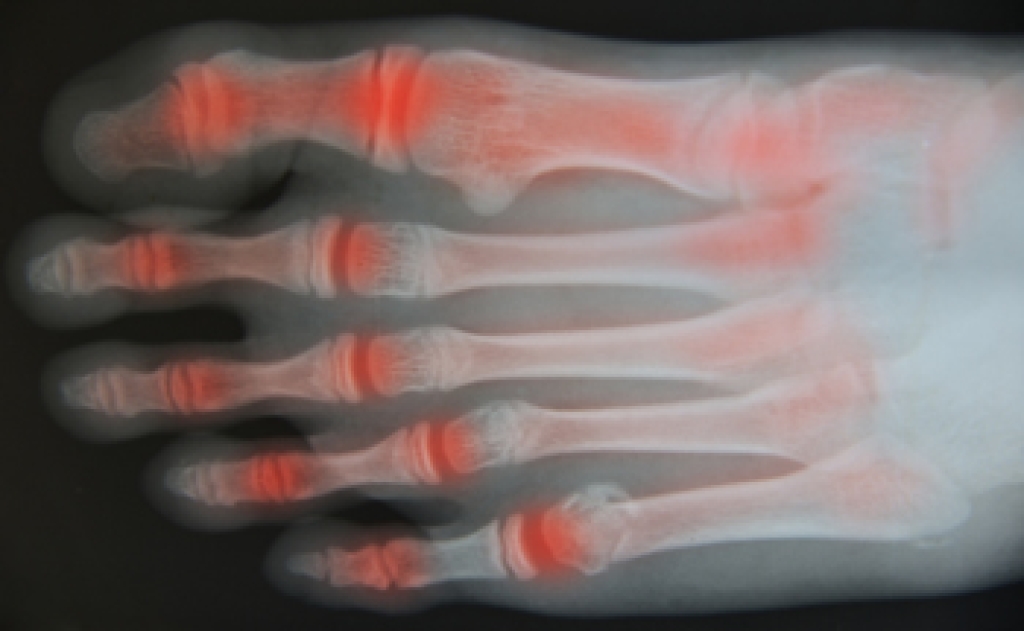

- Types of arthritis (rheumatoid, osteoarthritis, and gout)

Ways to Live with Arthritis

Many people suffer from the pain of arthritis, of which there are about 100 varieties. A podiatrist can help you figure out which form of this disease you have through a number of tests. The most common types are osteoarthritis, which is a wearing away of the cartilage between the bones; rheumatoid arthritis, a long-term condition that causes pain, swelling and deformity in the joints; and gout, caused by a buildup of uric acid that results in redness, swelling, and pain affecting the big toe and other joints. Among the ways you can live with arthritis are diet, exercise and pain management. It has been found that eating a Mediterranean style diet (fish, nuts, olive oil, vegetables and fruit) can help reduce the effects of arthritis. It is also suggested that you avoid red meat, poultry and full-fat dairy products, and try to include calcium rich foods to ward off osteoporosis (thinning of the bones). A regular program of exercise is suggested to help keep your weight down and reduce joint stiffness. A number of medications are available to alleviate the pain caused by arthritis. In addition, using heat or ice treatments as needed throughout the day and avoiding activities that increase your pain is suggested. Changing the way you operate with appropriate walking aids, raised toilet seats, and safely navigating in your home can be helpful. If you need more information on how to manage arthritis, please consult with a podiatrist for an examination and treatment options.

Arthritis can be a difficult condition to live with. If you are seeking treatment, contact Neeta Hasmukh, DPM from Total Podiatry. Our doctor can provide the care you need to keep you pain-free and on your feet.

Arthritic Foot Care

Arthritis is a joint disorder that involves the inflammation of different joints in your body, such as those in your feet. Arthritis is often caused by a degenerative joint disease and causes mild to severe pain in all affected areas. In addition to this, swelling and stiffness in the affected joints can also be a common symptom of arthritis.

In many cases, wearing ill-fitting shoes can worsen the effects and pain of arthritis. Wearing shoes that have a lower heel and extra room can help your feet feel more comfortable. In cases of rheumatoid arthritis, the arch in your foot may become problematic. Buying shoes with proper arch support that contour to your feet can help immensely.